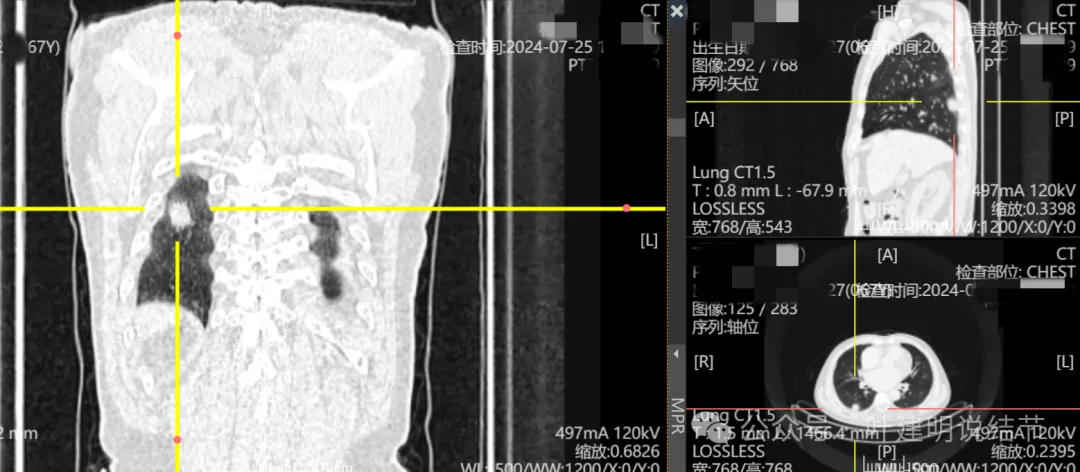

这是冠状位、矢状位与轴位的影像。